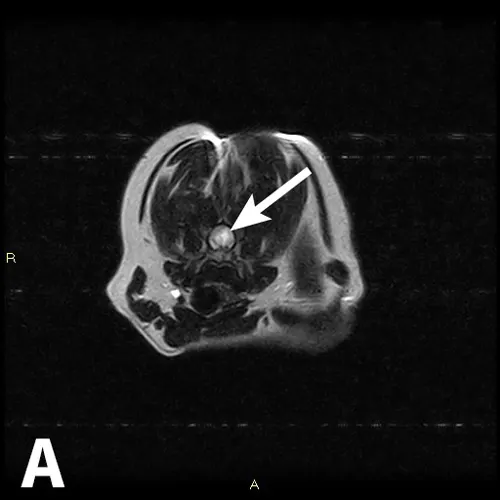

Figure 1

Magnetic resonance imaging (MRI) of the cervical spine: T2-weighted transverse image at the level of C6 (A) and T2-weighted midsagittal image (B). Evidence of hyperintensity within the spinal cord parenchyma (arrows) is consistent with a diagnosis of fibrocartilaginous embolism (FCE).

• Magnetic resonance imaging (MRI) of the cervical spine (Figure 1) showed a T2-weighted hyperintense slightly wedge-shaped left-sided lesion within the spinal cord, extending from the cranial aspect of C6 to the cranial aspect of C7. The intervertebral disks at C2-3 and C6-7 showed reduced signal intensity on T2-weighted imaging, consistent with dehydration. The most likely cause of the lesions seen was FCE and less likely ANNPE or primary inflammatory disease.